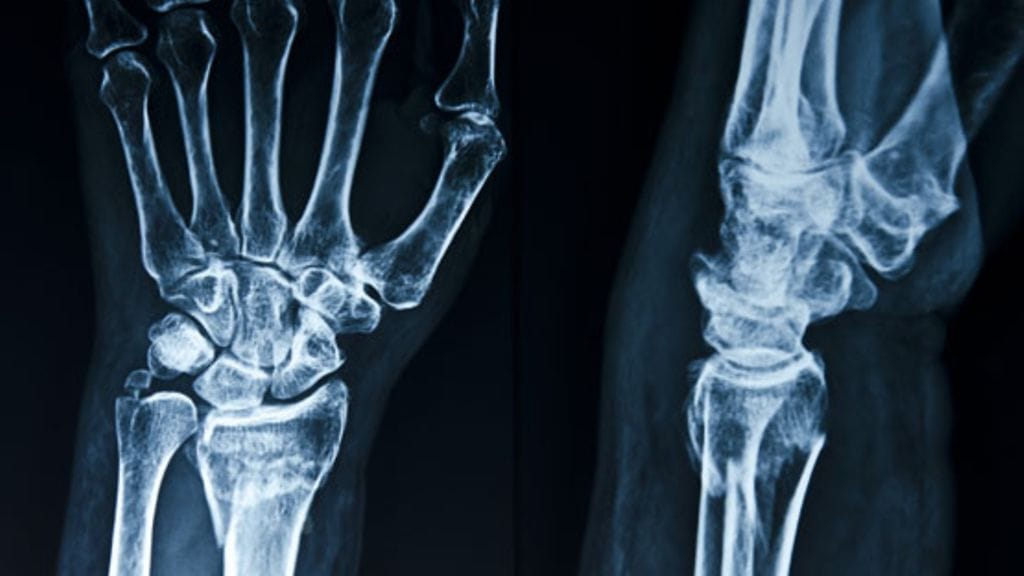

Studio55.fin kyselyyn vastanneista lukijoista yli 90 prosenttia kertoi kärsivänsä nivelkivuista. Monesta vastauksesta välittyi turhautuminen nivelvaivojen hoitoon: joko mikään ei tuntunut tepsivän tai lääkärin, lääkkeiden ja leikkausten koettiin vain pahentavan tilannetta. Osataanko nivelkipuja hoitaa?

Studio55.fi kysyi lukijoiltaan heidän nivelvaivoistaan. Ylivoimaisesti suurin osa, peräti 91 prosenttia yli 1 800 vastanneesta, kertoi kärsivänsä nivelkivuista. Moni vastaaja suhtautui kriittisesti ja epäluuloisesti lääkäreitä kohtaan tai kertoi saaneensa huonoa hoitoa. Tällaisia tarinoita lukijat kertoivat: